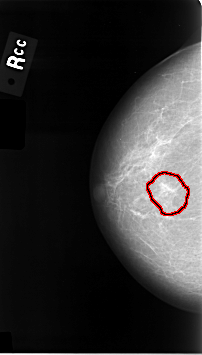

ics_version 1.0 filename C-0014-1 DATE_OF_STUDY 22 6 1992 PATIENT_AGE 83 FILM FILM_TYPE REGULAR DENSITY 1 DATE_DIGITIZED 11 9 1997 DIGITIZER LUMISYS LASER SEQUENCE LEFT_CC LINES 4648 PIXELS_PER_LINE 2696 BITS_PER_PIXEL 12 RESOLUTION 50 NON_OVERLAY LEFT_MLO LINES 4632 PIXELS_PER_LINE 2824 BITS_PER_PIXEL 12 RESOLUTION 50 NON_OVERLAY RIGHT_CC LINES 4608 PIXELS_PER_LINE 2624 BITS_PER_PIXEL 12 RESOLUTION 50 OVERLAY RIGHT_MLO LINES 4664 PIXELS_PER_LINE 2800 BITS_PER_PIXEL 12 RESOLUTION 50 OVERLAY |

FILE: C_0014_1.RIGHT_CC.OVERLAY TOTAL_ABNORMALITIES 1 ABNORMALITY 1 LESION_TYPE MASS SHAPE IRREGULAR MARGINS ILL_DEFINED ASSESSMENT 5 SUBTLETY 4 PATHOLOGY MALIGNANT TOTAL_OUTLINES 1 BOUNDARY |